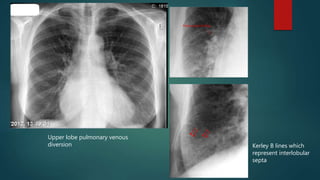

Pulmonary edema

 Pulmonary edema is caused by excess fluid in the lungs

 Causes of unilateral pulmonary edema:

 Re-expansion pulmonary edema

 Unilateral emphysema

 Unilateral pulmonary embolism

 Positioning

 Radiological findings: Vary

 Upper lobe vessel cephalization and increased cardiac size (cardiogenic cause)

 Peri-bronchial cuffing and Kerley B lines (interstitial edema)

 Batwing airspace opacification and air bronchogram sign (alveolar edema)

Unilateral re-expansion pulmonary edema Air bronchogram sign in unilateral

pulmonary edema secondary to

aspiration while laying on right side

Upper lobe pulmonary venous

diversion Kerley B lines which

represent interlobular

septa

Pulmonary edema  Pulmonaryedema is caused by excess fluid in the lungs  Causes of unilateral pulmonary edema:  Re-expansion pulmonary edema  Unilateral emphysema  Unilateral pulmonary embolism  Positioning  Radiological findings: Vary  Upper lobe vessel cephalization and increased cardiac size (cardiogenic cause)  Peri-bronchial cuffing and Kerley B lines (interstitial edema)  Batwing airspace opacification and air bronchogram sign (alveolar edema)

Unilateral re-expansion pulmonaryedema Air bronchogram sign in unilateral pulmonary edema secondary to aspiration while laying on right side

Upper lobe pulmonaryvenous diversion Kerley B lines which represent interlobular septa